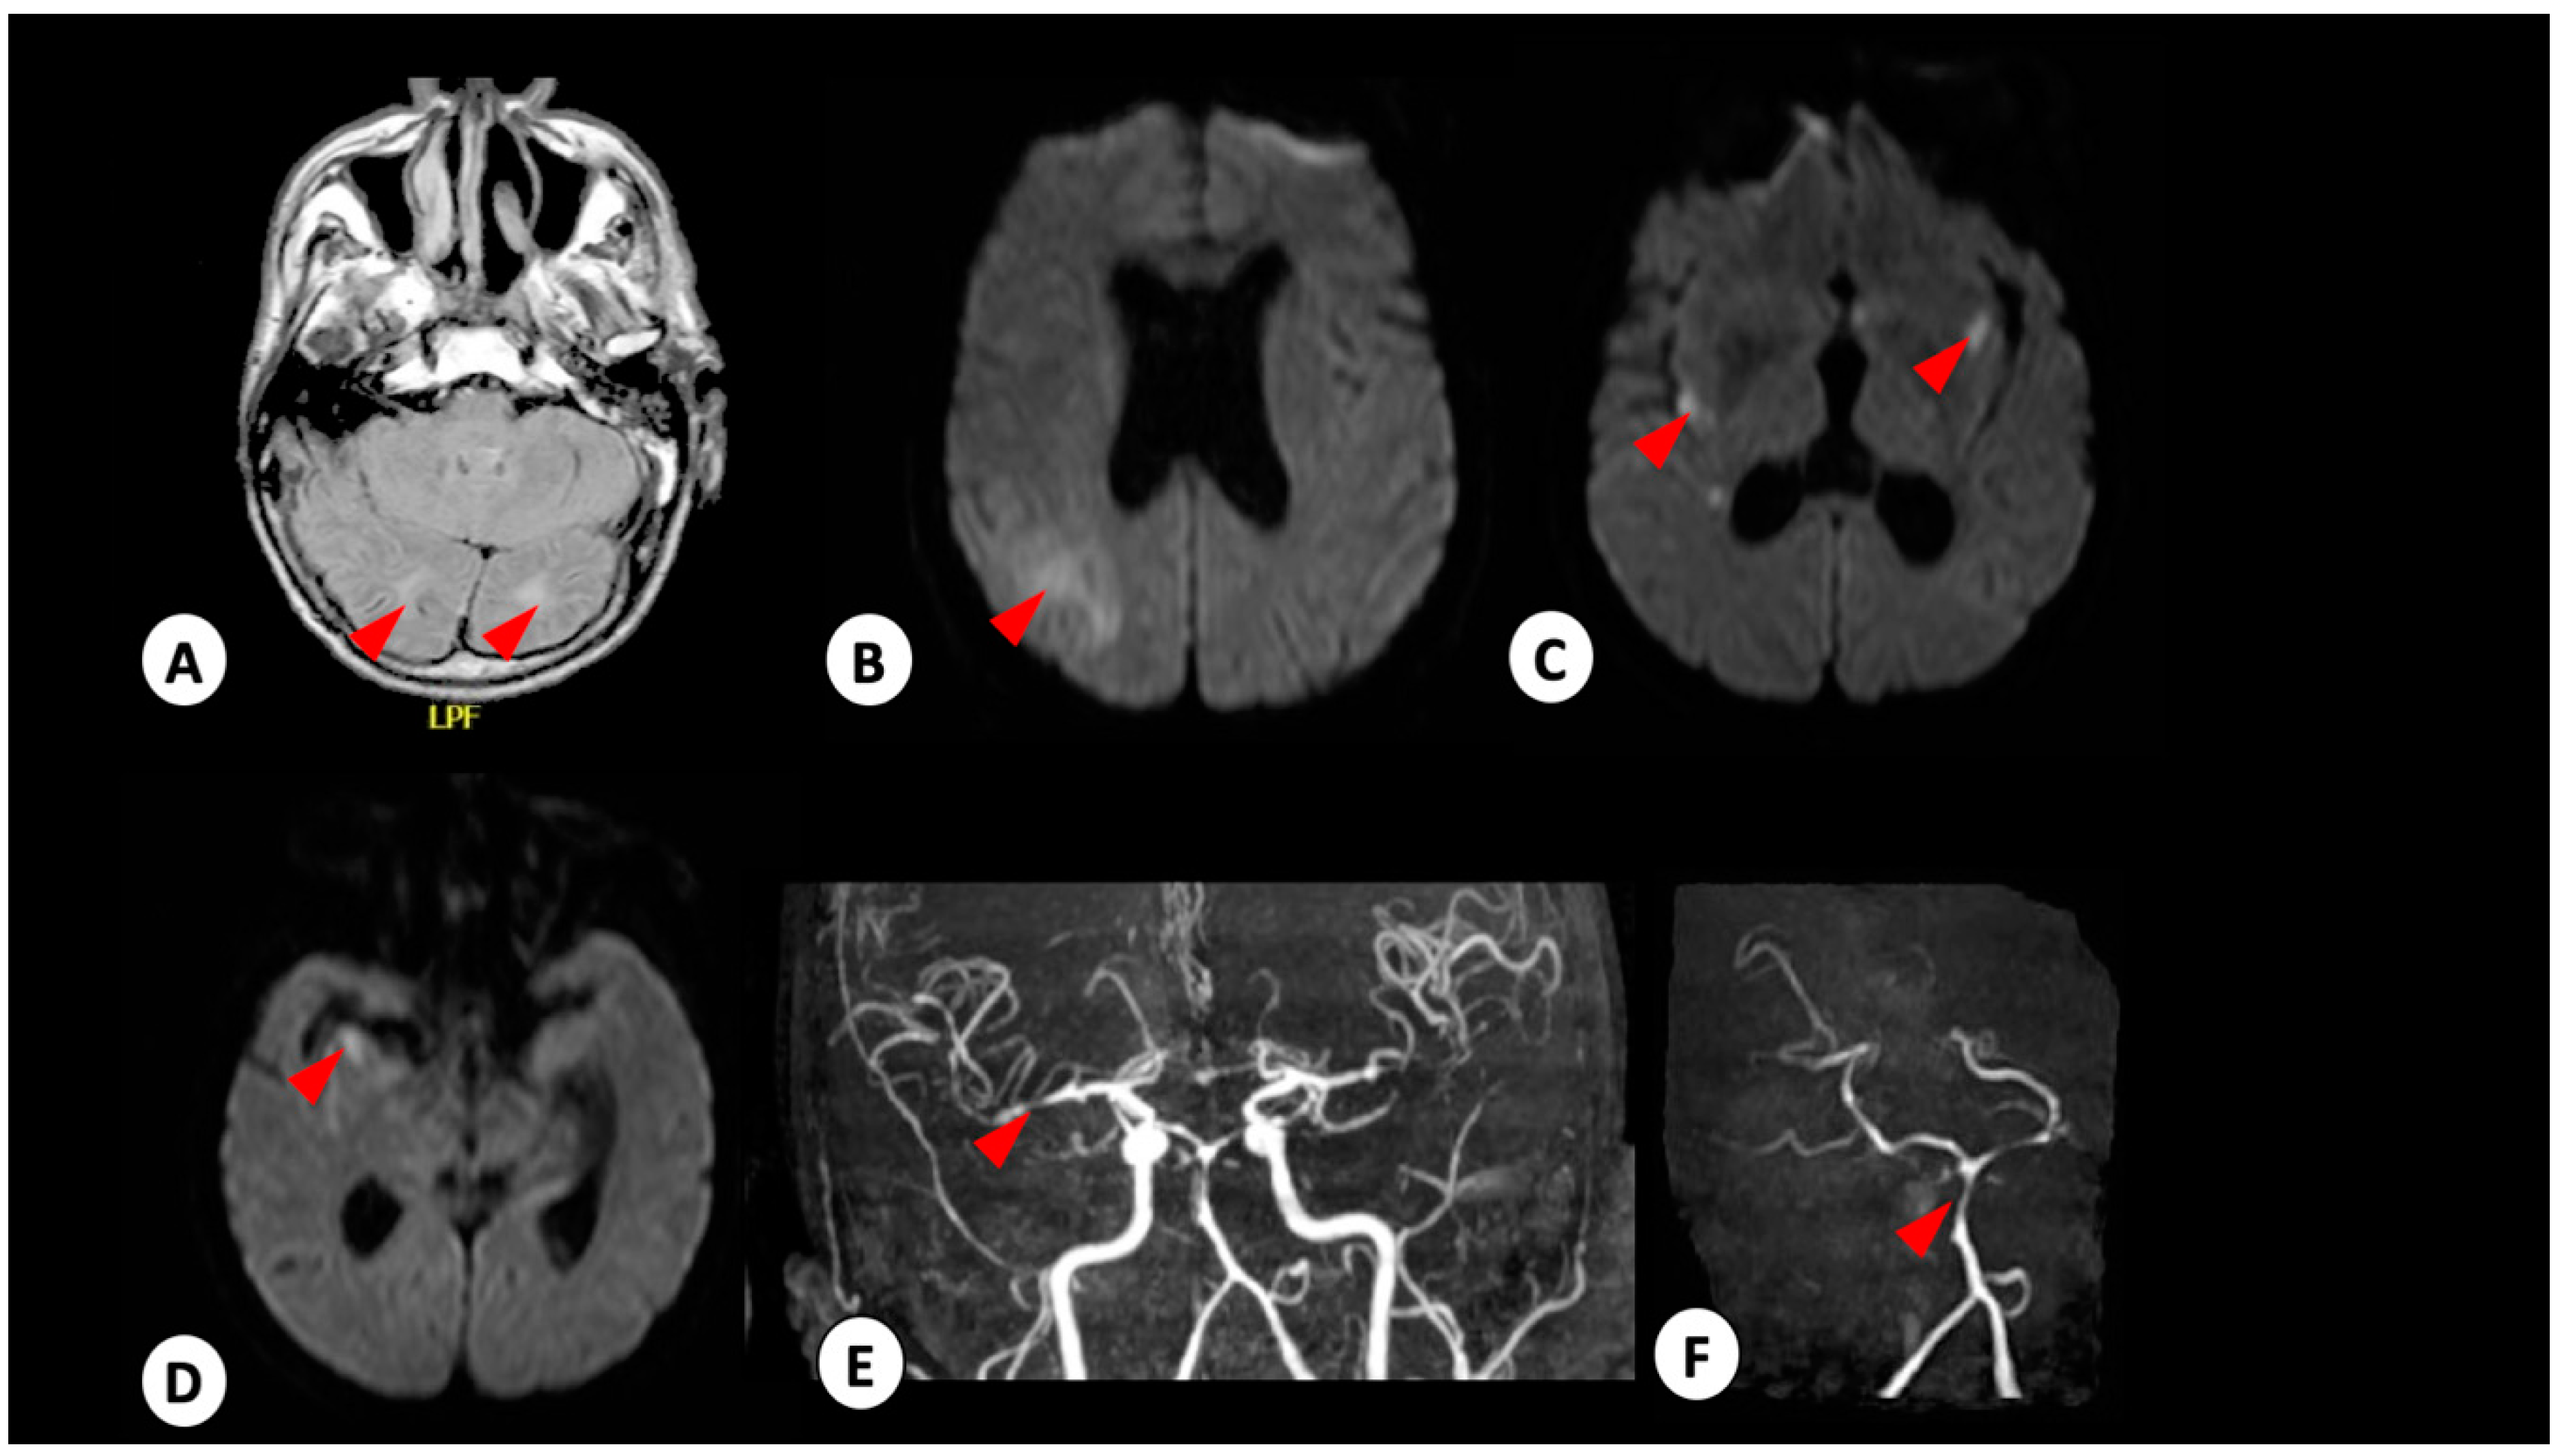

3.1. Case 1

3.2. Case 2

3.3. Case 3